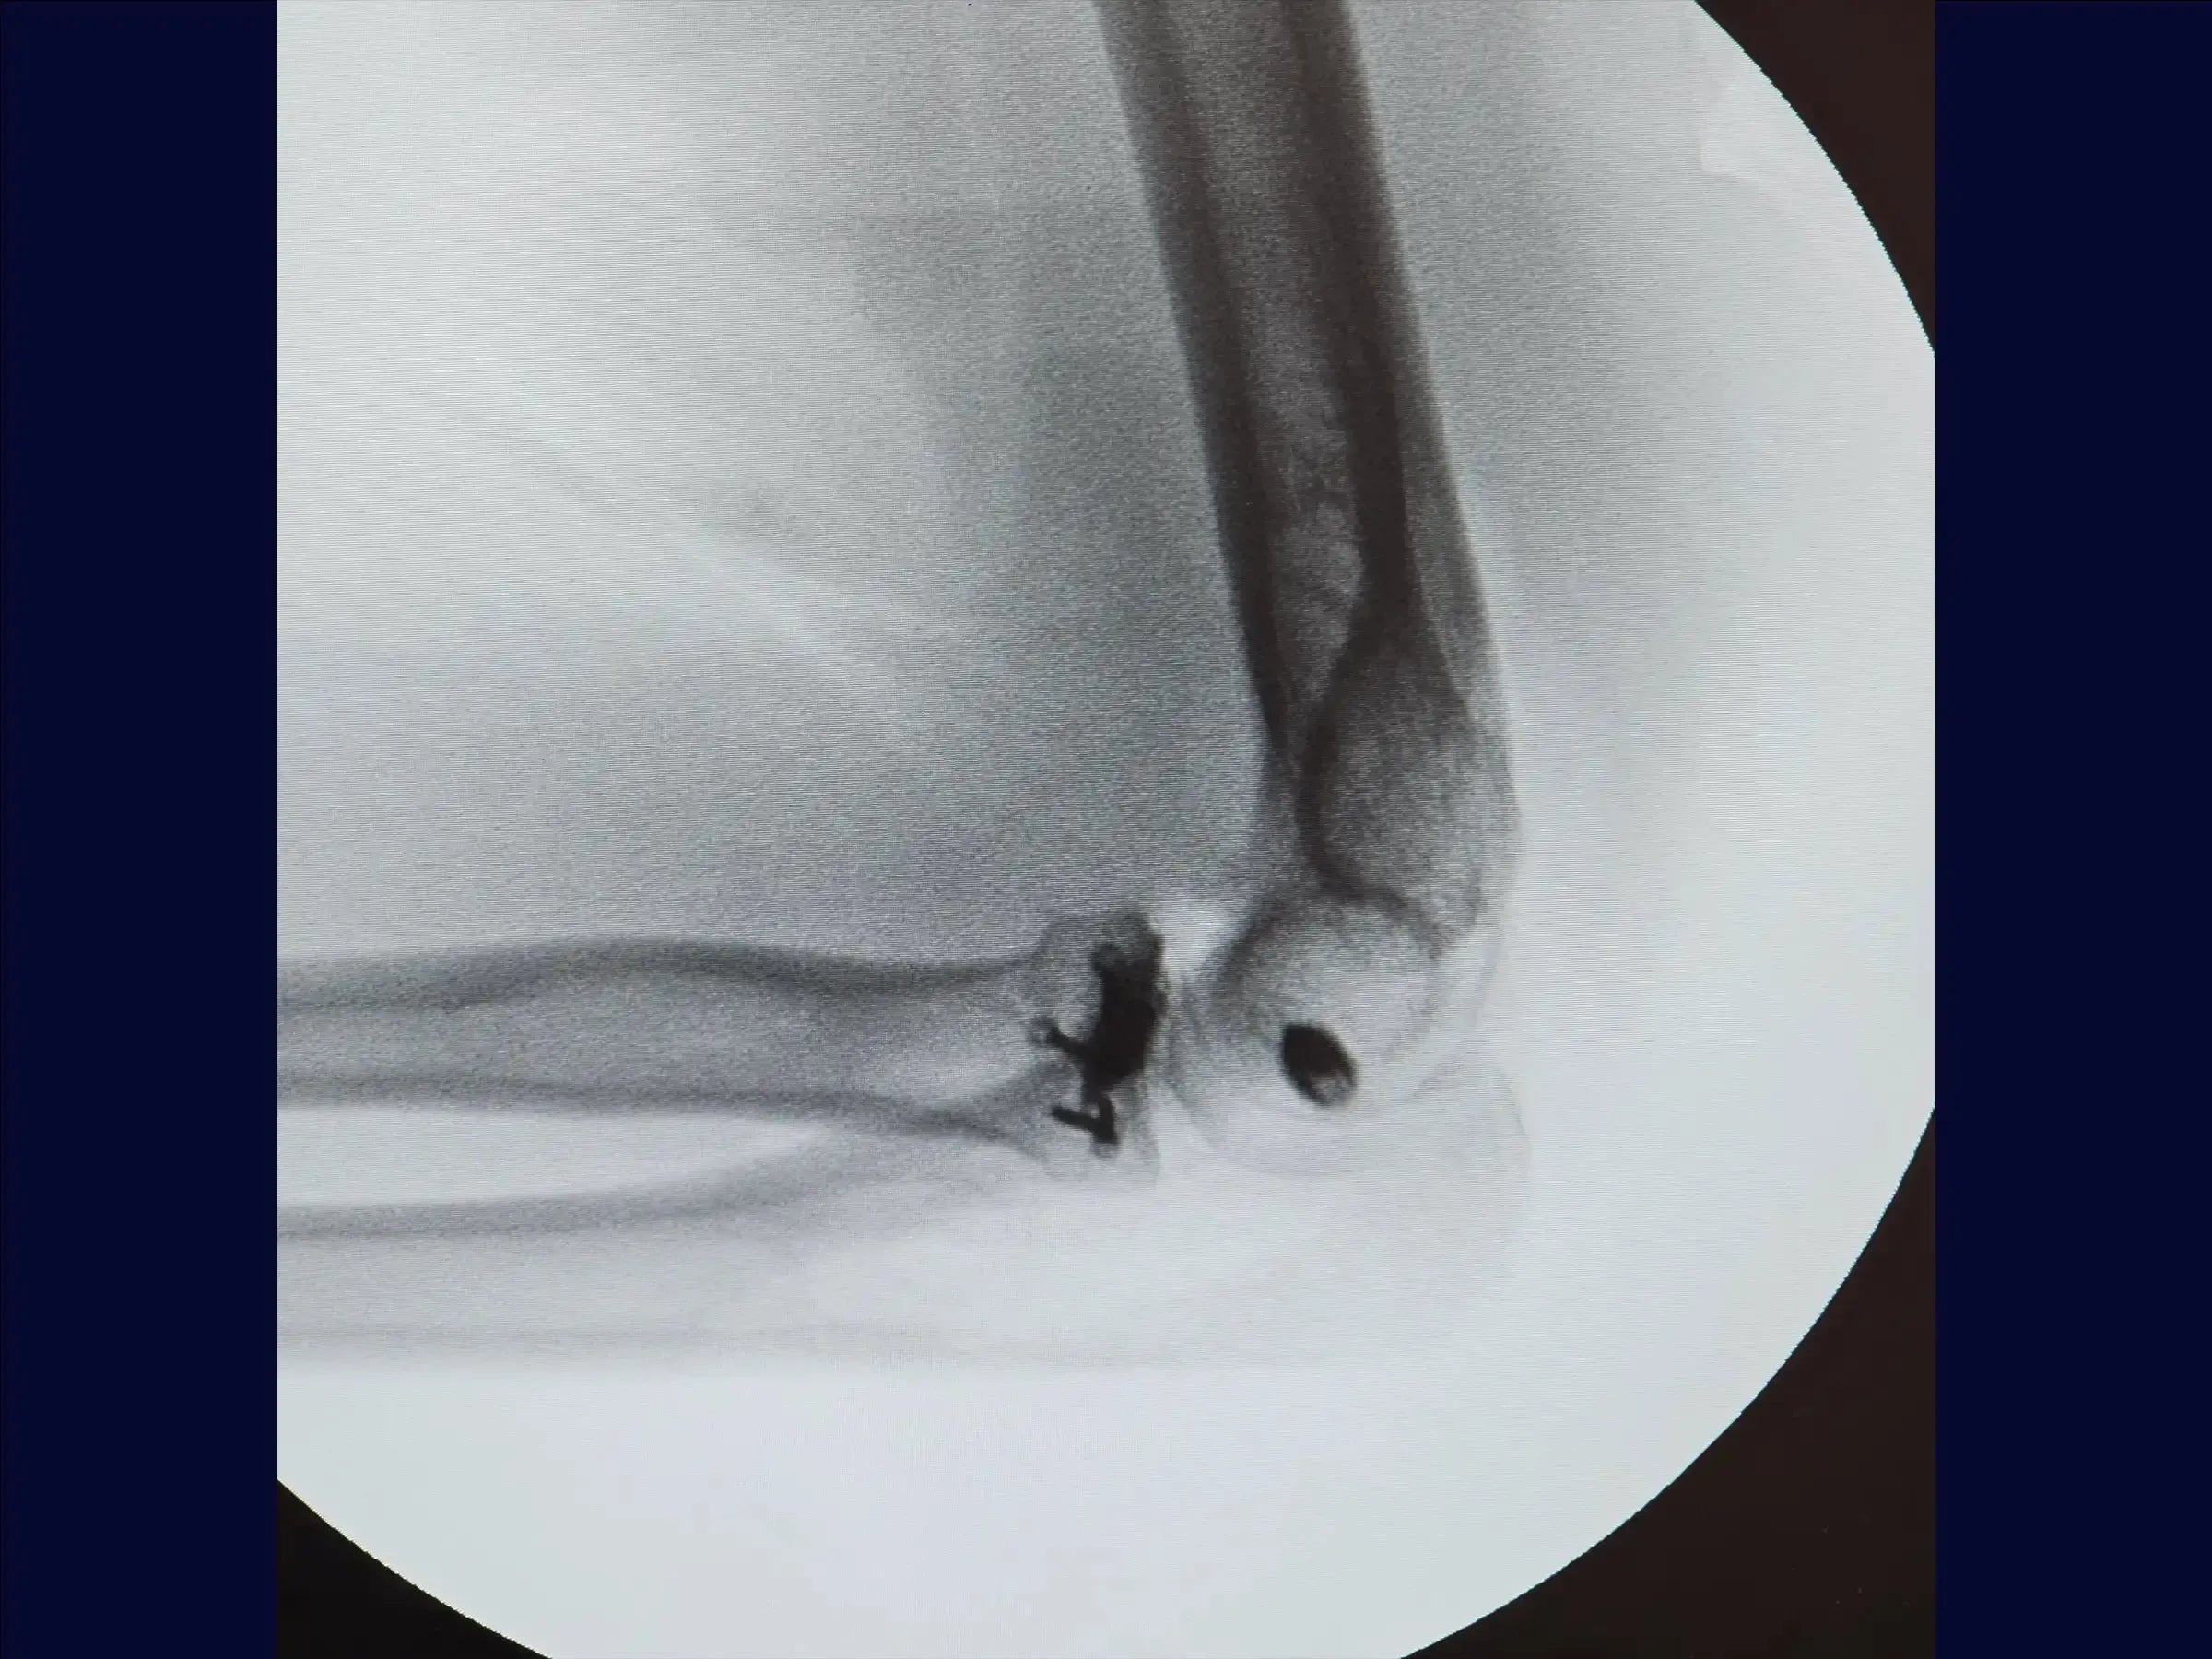

- Evaluación y planificación inicial: Interpretar radiografías para identificar fracturas complejas (Mason 3) y compromiso articular. Planificar siempre la reparación del ligamento y tener una prótesis disponible como alternativa.

- Evaluación de la fractura : Decidir entre osteosíntesis o artroplastia según la respuesta del periostio a la tracción de los fragmentos.